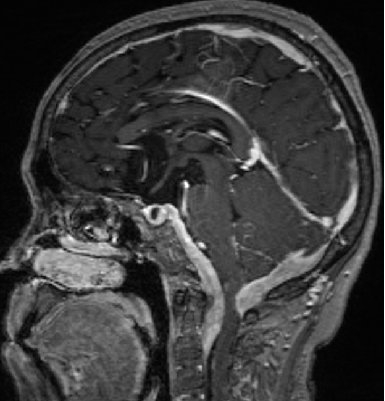

2015-4-1 MRI

2013-5-16

2013-8-2

2014-12-13

2015-4-1

2015-4-3